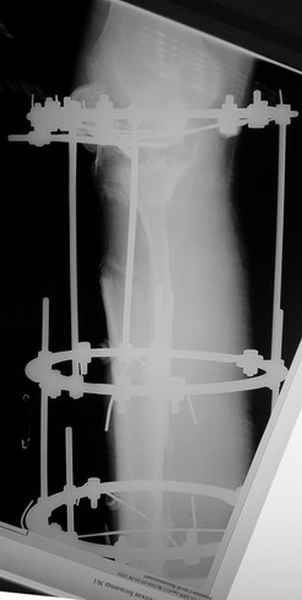

Пациент В. 53 лет, травма в феврале 2009. ДЗ. Открытый оскольчатый перелом нижней трети голени. При боли поступлении выполено ПХО, аппарат Илизарова. В последующем проводили ВХО, резекция костных отломков, укорочение 6 см, рана зажила. Была выполнена остеотомия большеберцовой кости в проксимальном отделе, резекция. Производилось тракция. На последних рентгенограммах выявлено, что одновременно с "выращиванием" регенерата произошло низведение надколенника на длину выращенного регенерата. Клинически: активное разгибание сохранено, объем движений в колене 180-110 градусов. Черными стрелками обозначен верхний край надколенника с одной и с другой стороны. Красная стрелка обозначает пальпируемую связку надколенника. Причина - остеотомия выше места прикрепления связки надколенника. Вопрос: была ли у кого подобная ситуация? Что делать? При первом обдумывании приходит решение: отсечение места прикрепления связки надколенника с костным блоком, перемещение на "правильное" место, укорочение сухожилия четырехглавой мышцы.

По снимкам - плотность регенерата хорошая, сложностей с фиксацией в него костного "основания" быть не должно.

К сожалению, подобное осложнение "нет-нет да и возникает" при удлинении, коррекции деформации голени. В англоязычной литературе оно описано как "patella baja". Один из вариантов лечения - проксимальное перемещение надколенника приемами чрескостного остеосинтеза.

Я бы уменьшил диастаз между фрагментами сантиметра на два. Судя по снимкам, регенерат это может позволить.

Я бы присоединился к предложению А.Артемьева - уменьшить диастаз, и посмотреть можно будет, как поведет себя надколенник.

Чтобы не сталкиваться с таким осложнением, лучше удлинять большеберцовую кость на уровне диафиза. Тогда еще и интрамедуллярный стержень будет удобнее вводить по завершении удлинения ;-)